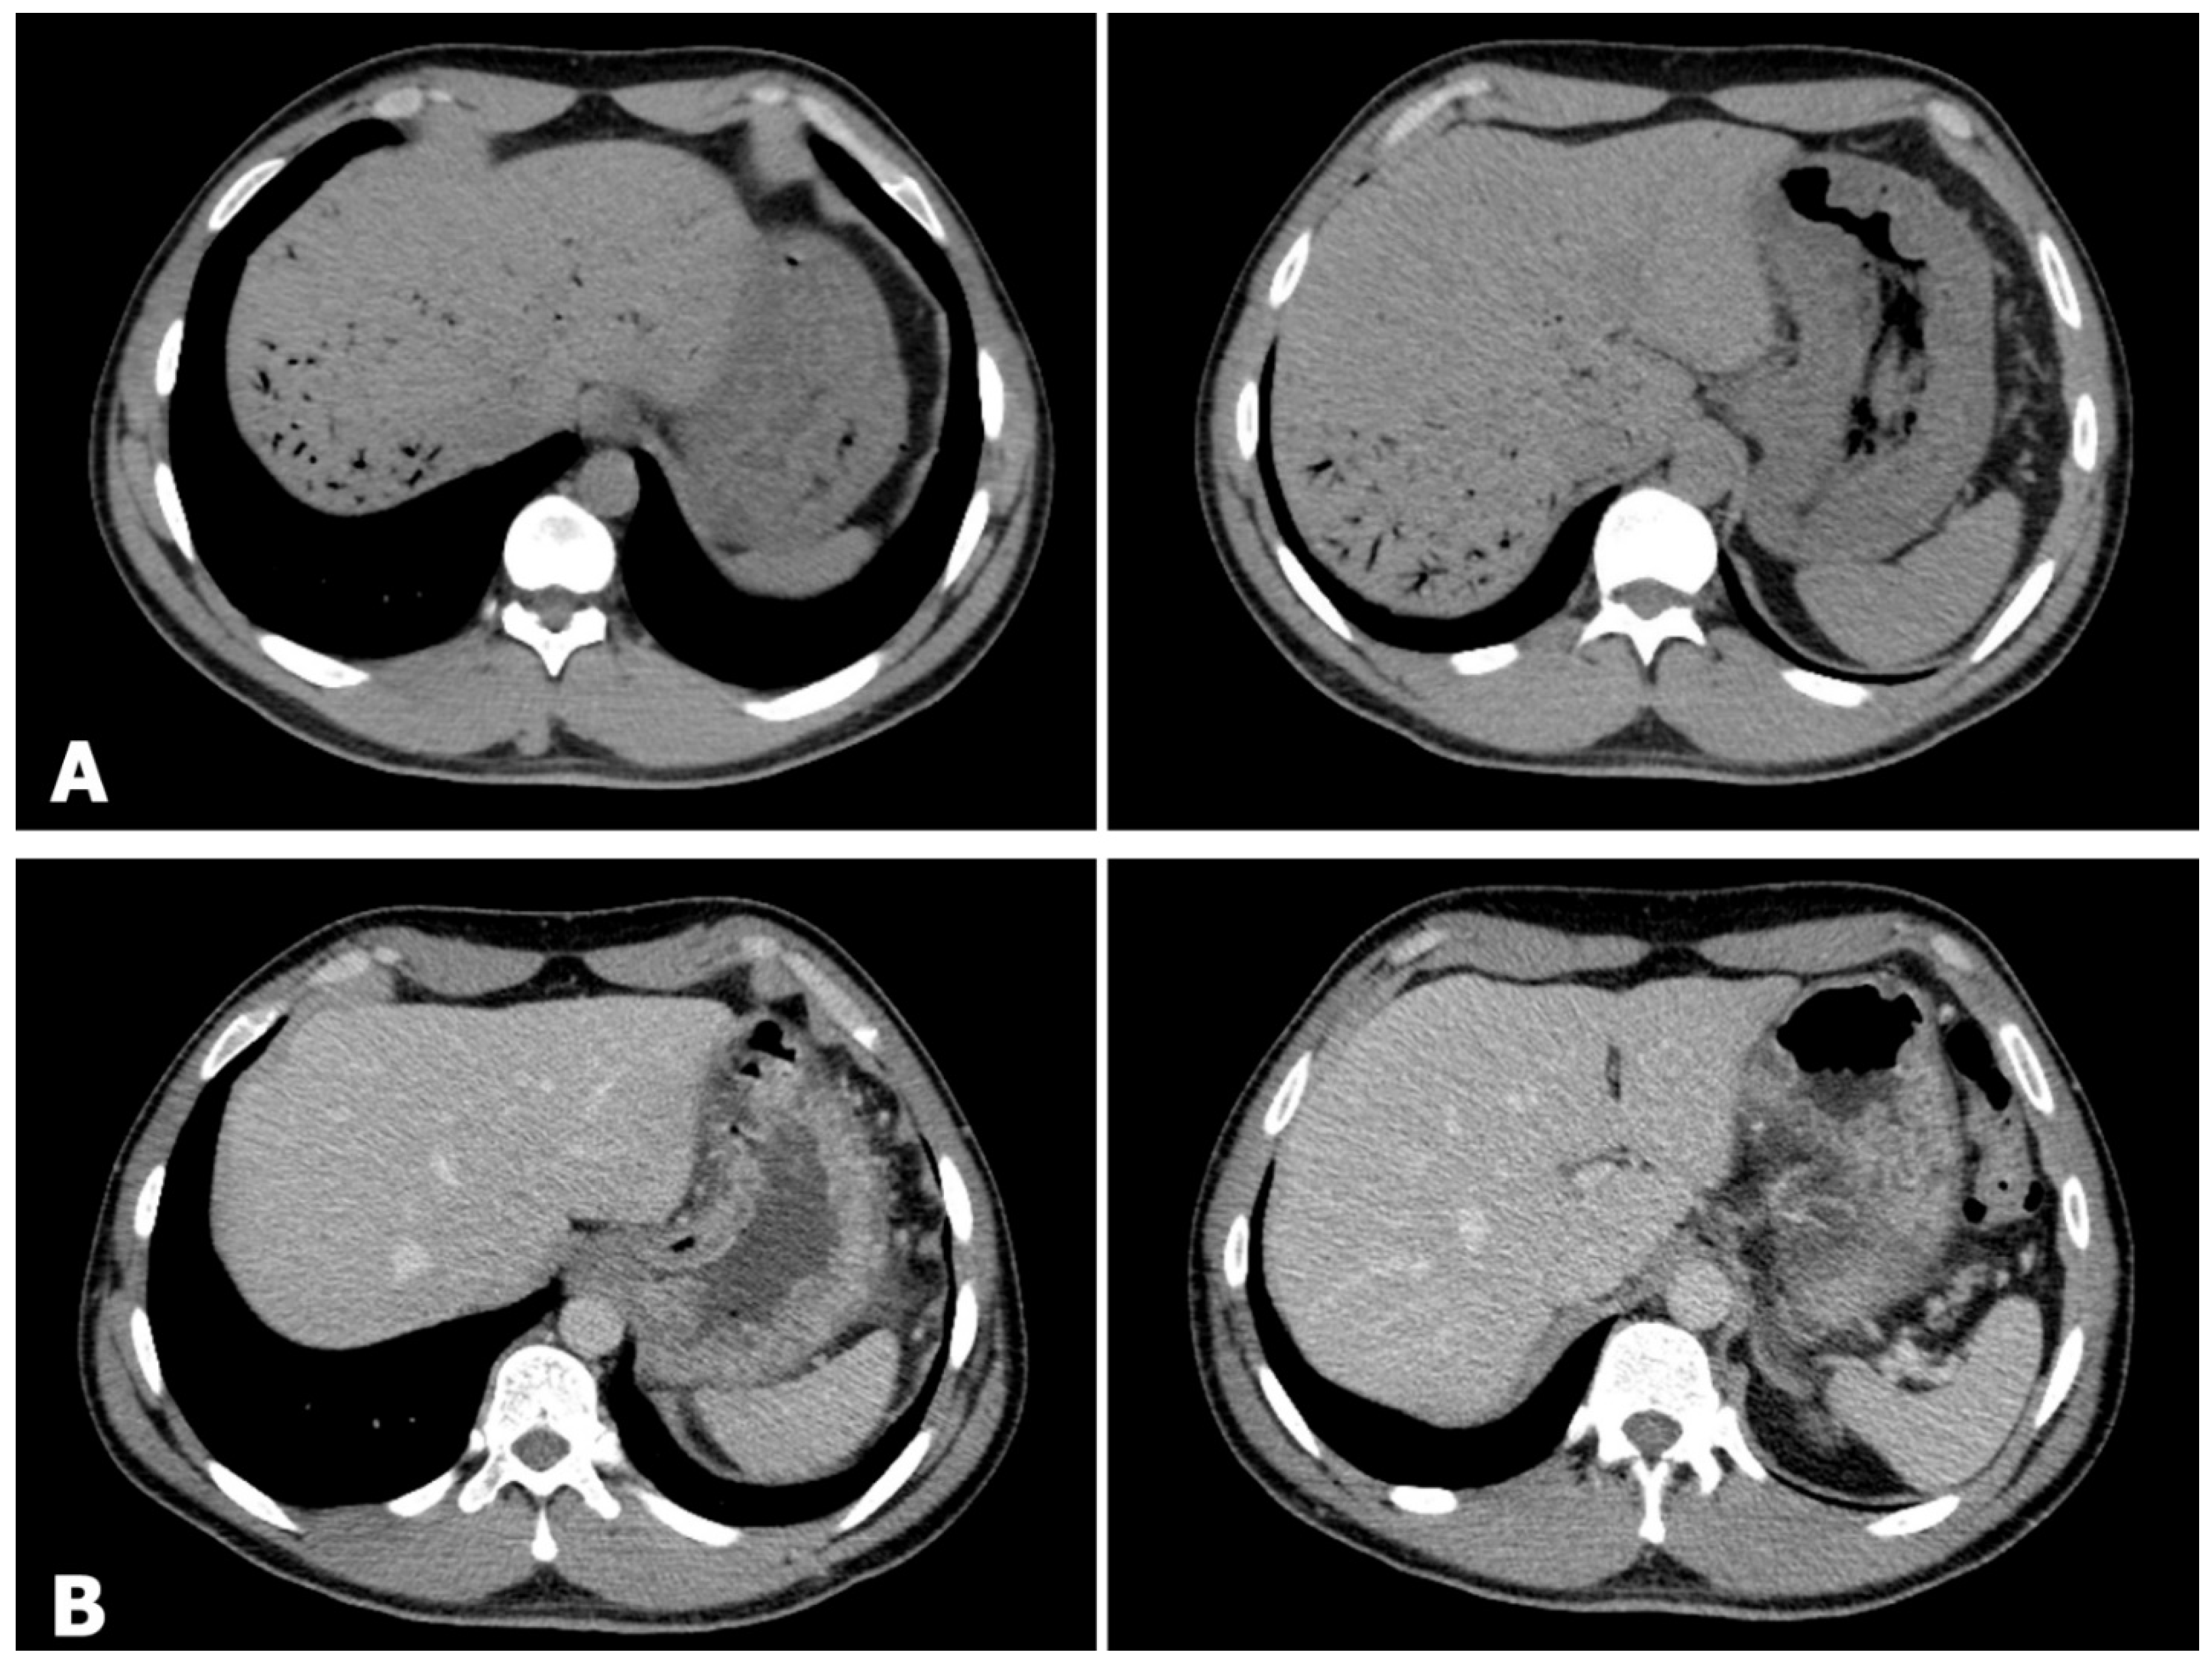

Hepatic Portal Venous Gas (HPVG) after Ingestion of Chlorine Bleach: A Transient Phenomenon

Arico, F.M.; Buemi, F.; Pitrone, P.; Giardina, C.; Trimarchi, R.; Borruto, F.; Doria, S.; Turiaco, C.; Caloggero, S. Hepatic Portal Venous Gas (HPVG) after Ingestion of Chlorine Bleach: A Transient Phenomenon. Diagnostics 2023, 13, 3615. https://doi.org/10.3390/diagnostics13243615